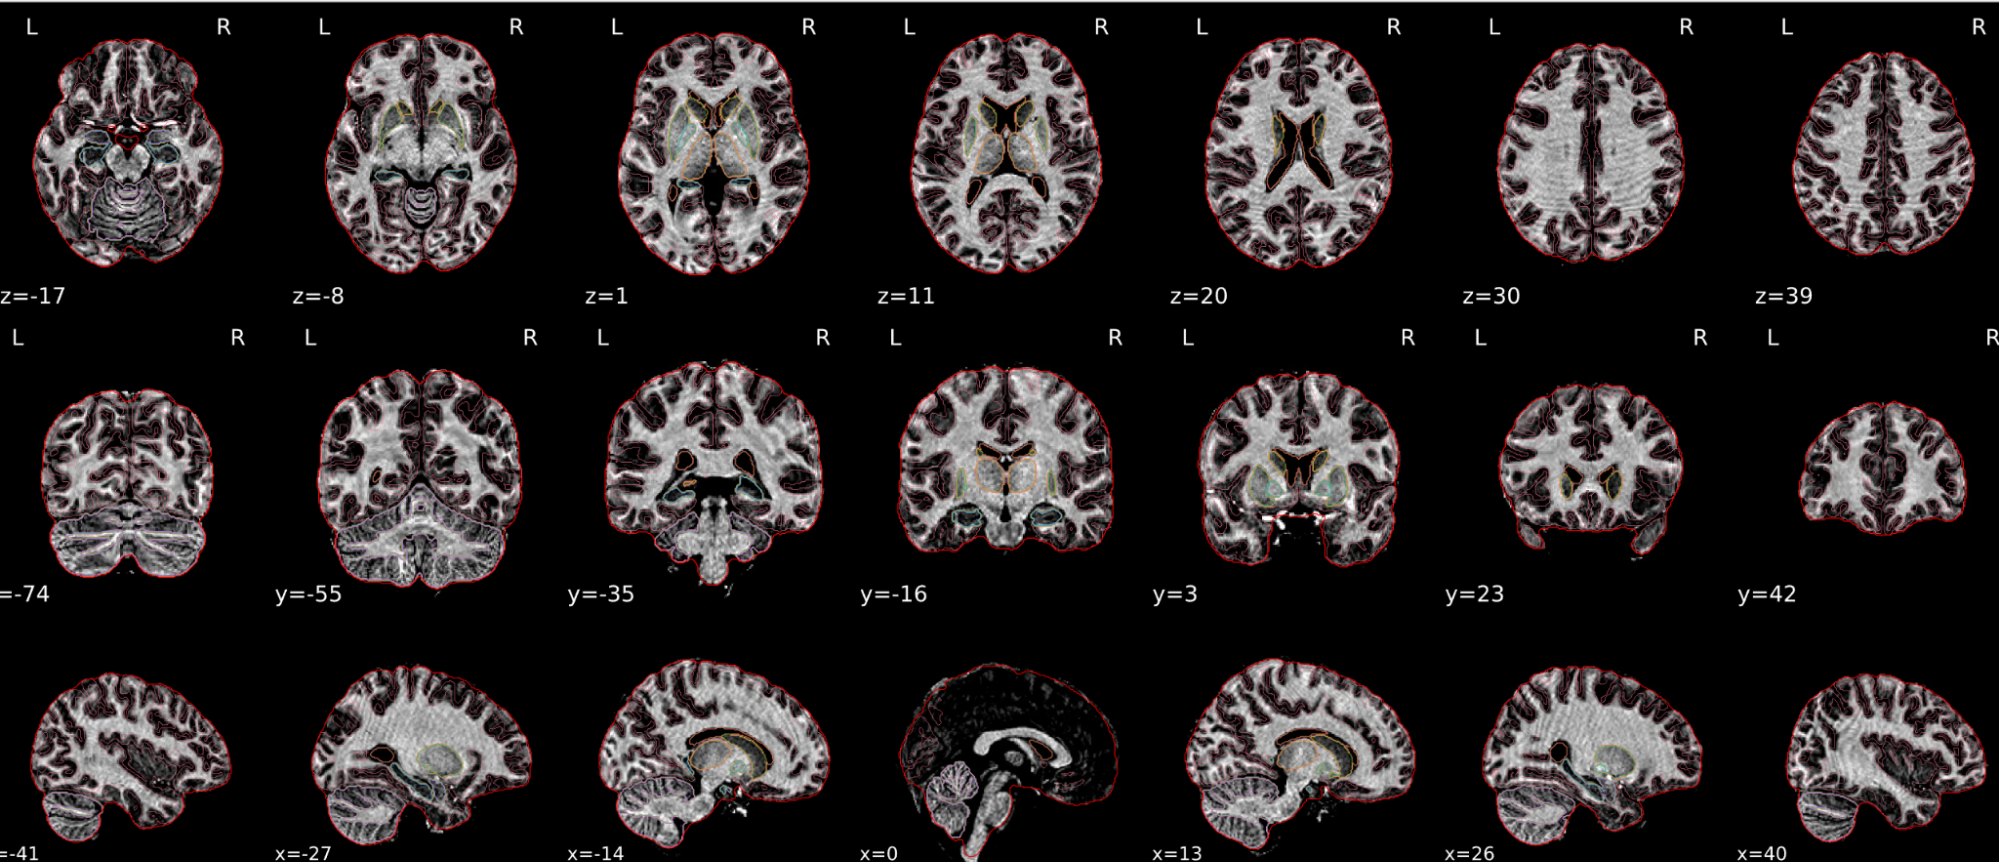

EPI tSNR

In the signal to noise ratio images of the resting state image the desired signal is compared to the amount of background noise. It is important to check all the views (sagittal, coronal, axial) because some artefacts (e.g., stripes) may be evident only in one particular view.

Example of a good subject

- Signal to noise is symmetrically distributed and there is no signal distortion

Example of a bad subject

- Asymmetry

- Potential signal distortion (might represent an artefact)

- Signal drop-out

- Stripes artefact

Clear large artefact (e.g., zebra stripes in example 1) are worth the exclusion of the subject. If you are unsure, check the other quality metrics for that subject to decide whether they should be excluded.

Summary

| good | bad |

|---|---|

| Symmetrical distribution of noise and signal | Asymmetry |

| No disruptions of the signal (no “black patches”) |

Potential signal disruptions (could be related to artefacts) |

| No stripes (sign of high motion) |

Signal drop |

| Stripe artefacts (“zebra” stripes due to motion) |